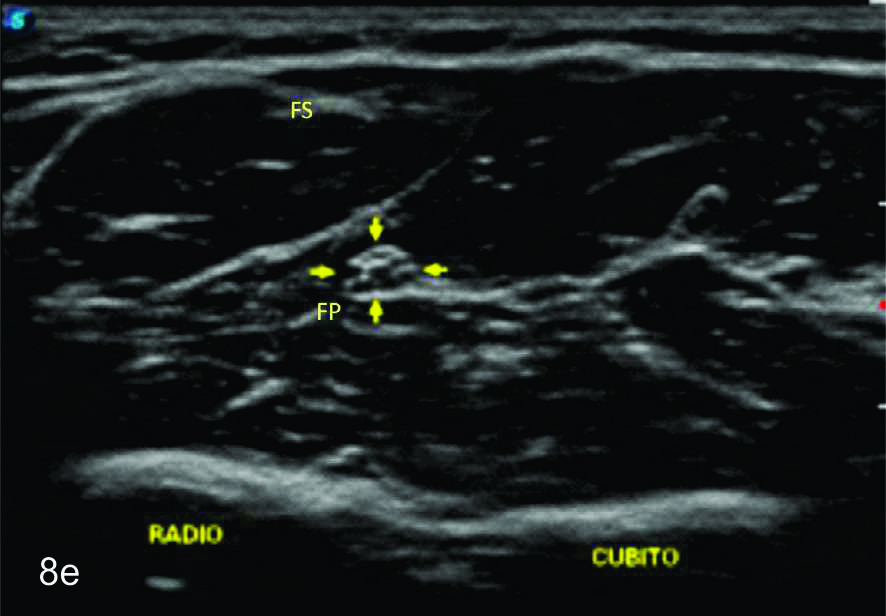

Figura 16

Tumor del nervio radial a nivel del brazo derecho.

A- Se observa un corte longitudinal del nervio radial proximal a la lesión (flechas blancas abiertas), se observa como el mismo se encuentra levemente engrosado y como se continúa con la masa en estudio (flecha amarilla). B- Corte transversal del mismo paciente en donde se identifica un tumor homogéneo ligeramente hipoecogénico y bien delimitado de los planos musculares adyacentes (flechas blancas abiertas).